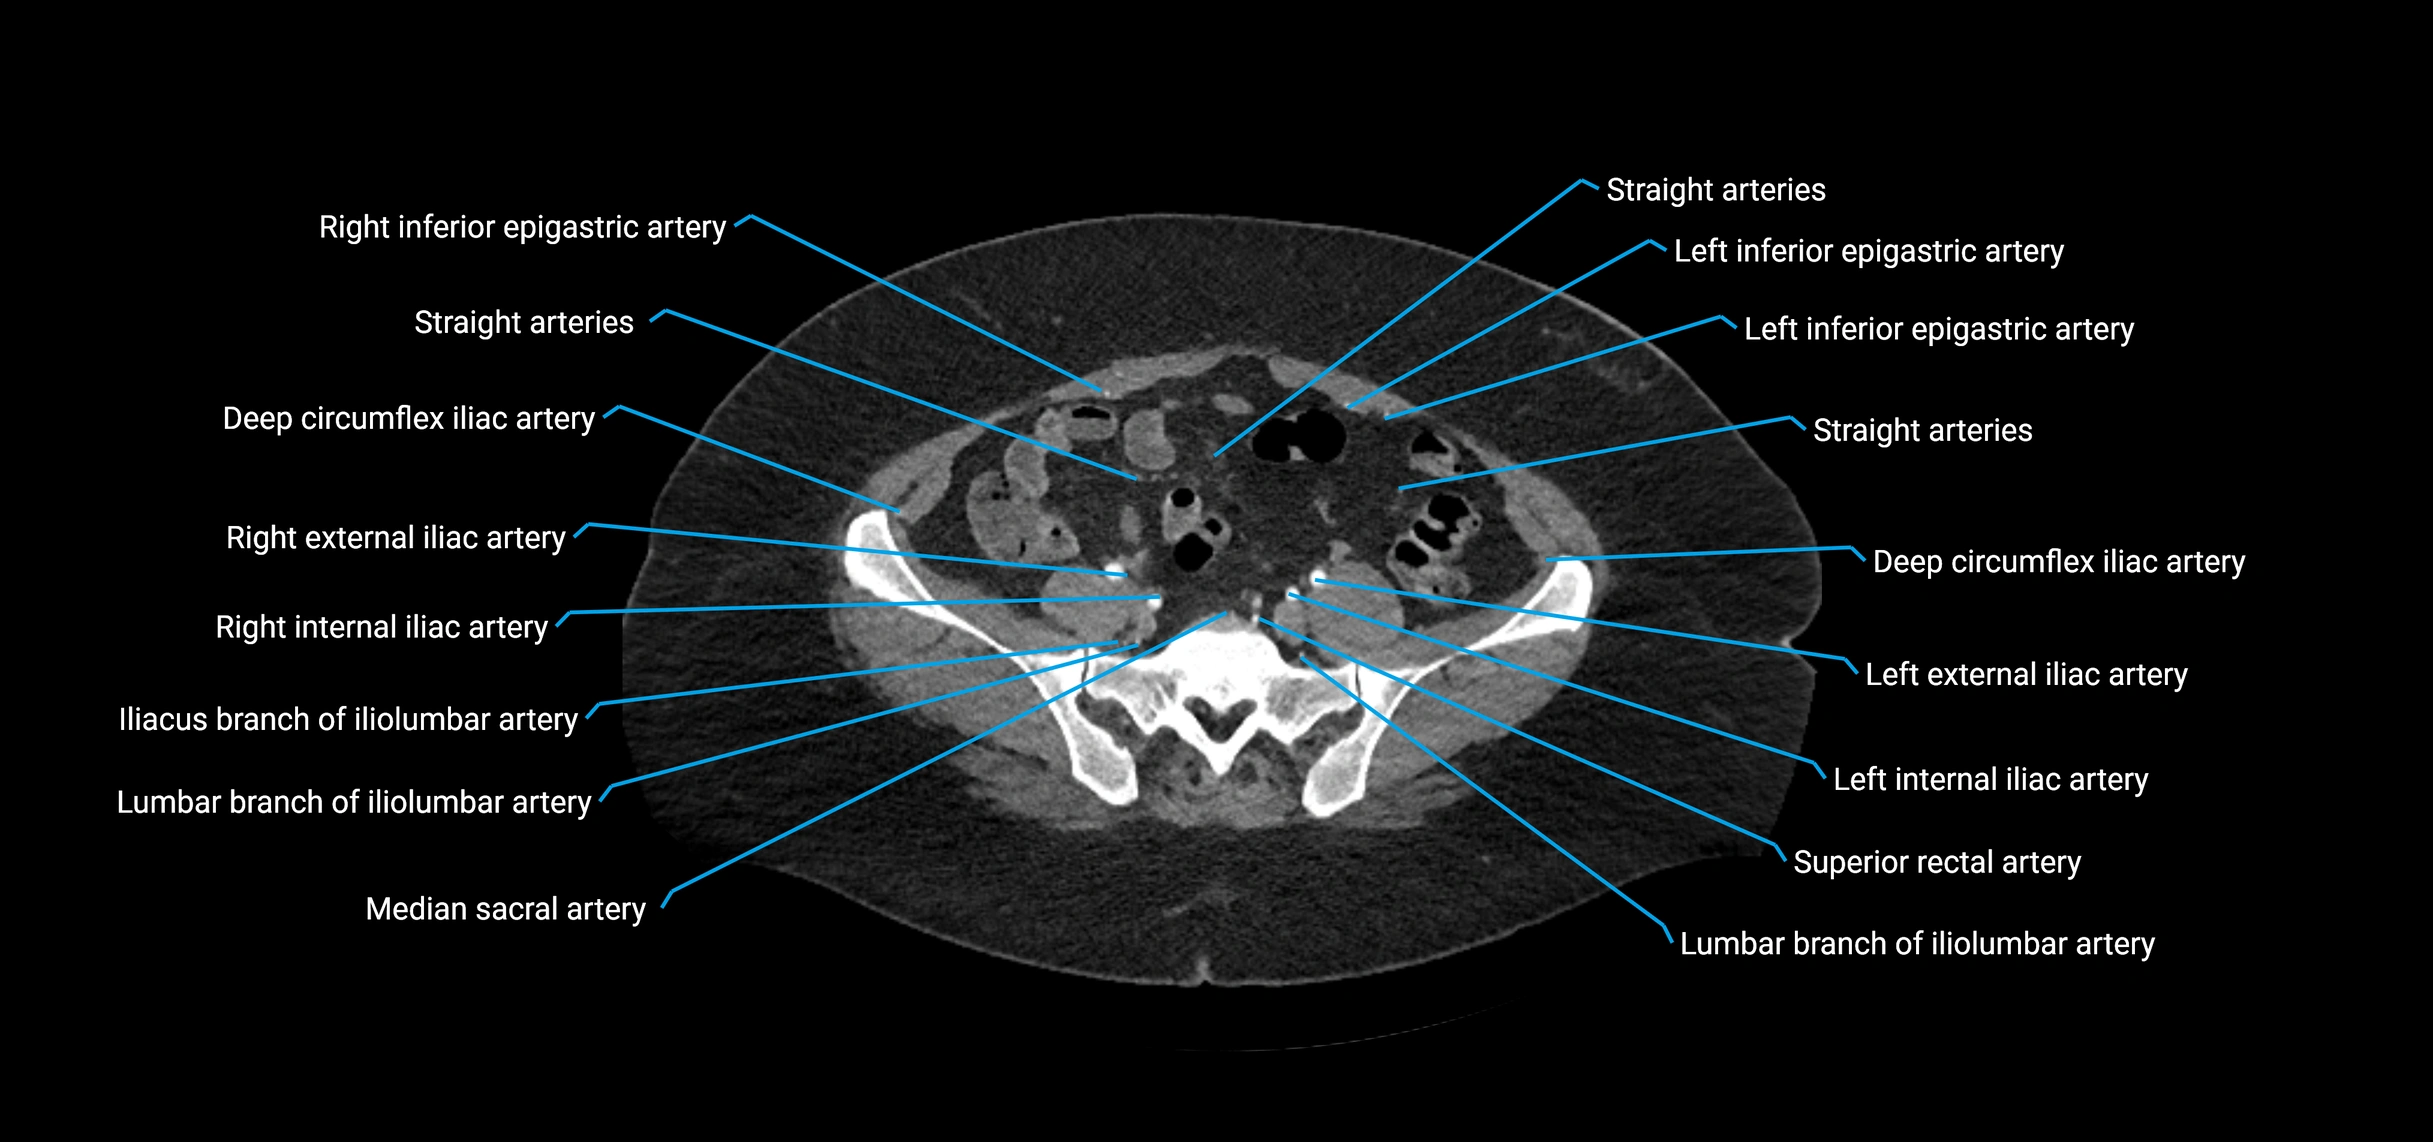

Contrast-enhanced CT (CTA):

• Gold standard for abdominal aortic imaging

• Provides excellent detail of lumen, wall, aneurysm, thrombus, and branch vessels

• Multiplanar and 3D reconstructions help in aneurysm measurement, stent graft planning, and dissection evaluation

• Detects acute rupture, traumatic injury, or occlusion with high sensitivity